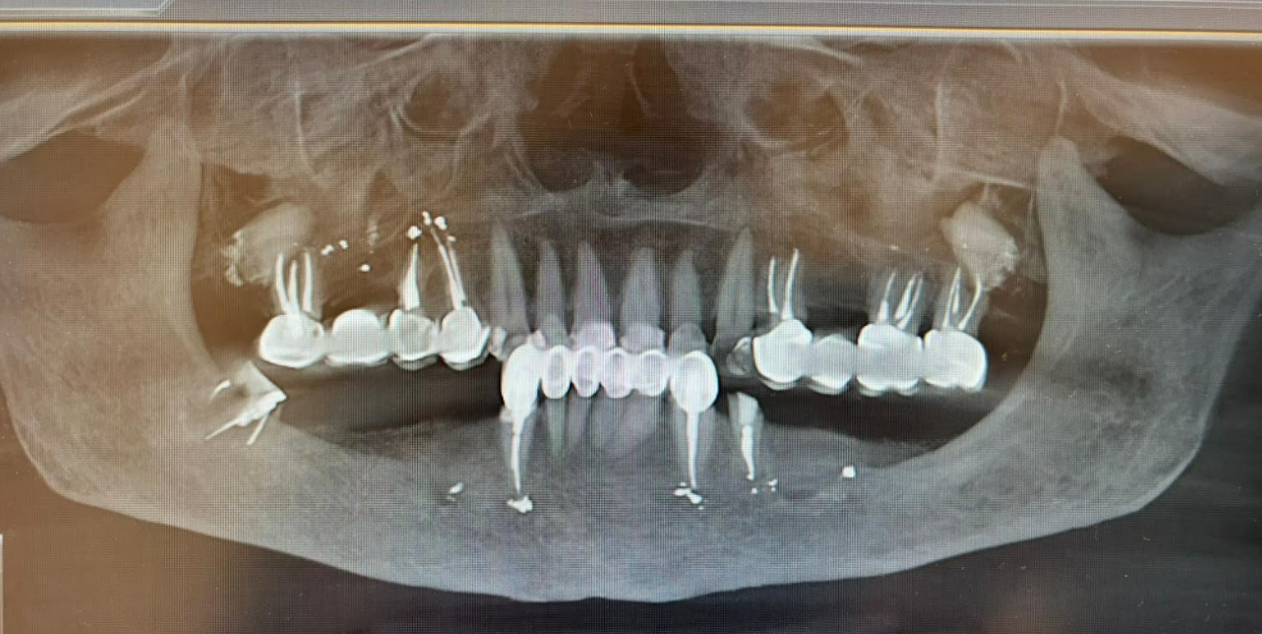

In the first stage, hopeless teeth #34 and #48 were extracted. Immediate implant placement was performed: six implants were placed, three in the third quadrant and three in the fourth quadrant. A surgical guide was used to ensure precise implant positioning. The implant-abutment interface utilized a standard Internal Hex connection.

Immediately following implant placement, V-Type Multi-Unit Abutments were placed, and healing caps were secured onto them. The abutment cuff height was selected based on mucosal thickness and alveolar ridge anatomy. XGATE, a company specializing in innovative prosthetic solutions, incorporates digital height markings on V-Type abutments (see illustration below).

The image below, taken after soft tissue healing, clearly displays the placed V-Type Multi-Unit Abutments (MUA V-Type) and their respective positions:

| Tooth Position (FDI) | MUA Type & Gingival Height |

|---|---|

| #34 | MUA – 3 mm |

| #35 | MUA – 2 mm |

| #37 | MUA – 1 mm |

| #44 | MUA – 1 mm |

| #45 | MUA – 2 mm |

| #47 | MUA – 2 mm |

| Total: 6 Positions | 6× MUA |

During the soft tissue healing and osseointegration period, the patient adhered to a soft diet. Upon complete healing and re-evaluation of all clinical parameters, zirconium dioxide bridges were fabricated and delivered.